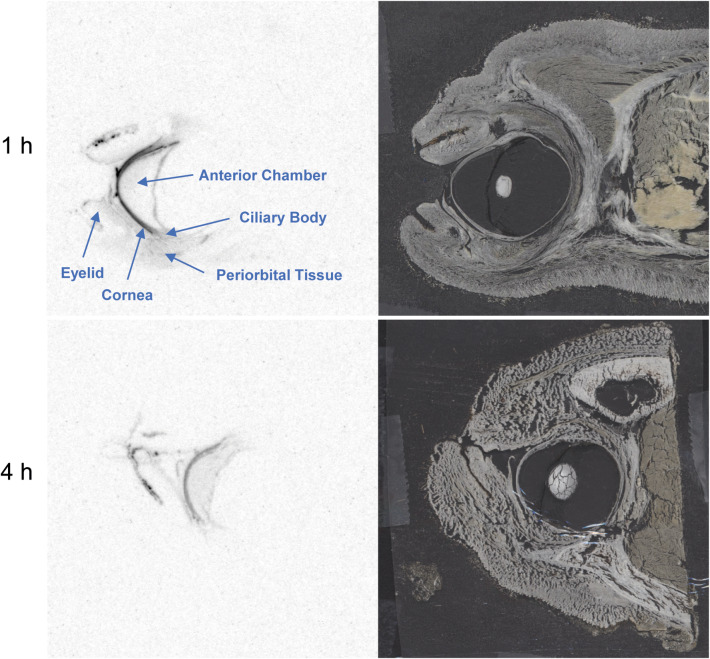

Figure 1 shows representative sections and autoradiographs from in situ eyes of animals that received five daily topical doses of 14C-latanoprost. Radioactivity appeared to be diffusely distributed throughout the anterior portion of the eye at 1, 4, and 24 h after the last dose. Radioactivity was present in the bulbar conjunctiva, cornea, anterior chamber, iris, ciliary body, upper and lower eyelids, and periorbital tissues (fat and muscle) after topical administration (Fig. 1).

Fig. 1.

Representative sections of fresh-frozen eyes in situ (right) and corresponding autoradiographs (left) from beagle dogs that received five daily topical ophthalmic bilateral administrations of 14C-latanoprost. Eyes in situ were collected at 1 and 4 h after the last administration. Annotations identify tissues and areas of interest